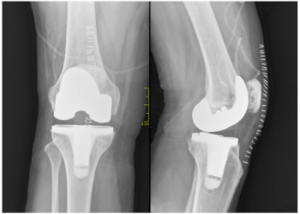

Total Knee Replacement - Dr. Pramod Kumar Surve

Meet Dr. Pramod Kumar Surve, a distinguished Orthopedic surgeon specializing in Orthopaedic Surgery, Spine Surgery, Trauma Surgery, and Joint Repla...